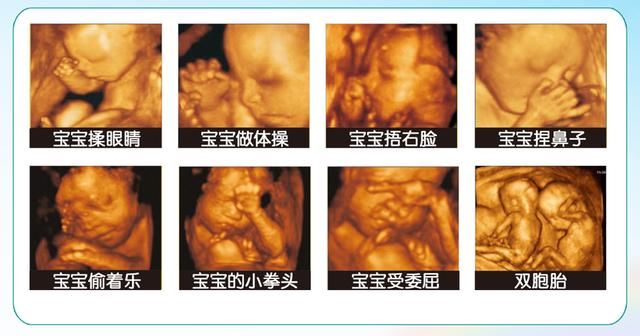

3.四维超声

根据超声方法监测胎儿生长发育情况,了解胎儿各器官构造及羊水、胎盘情况,筛查胎儿畸形。